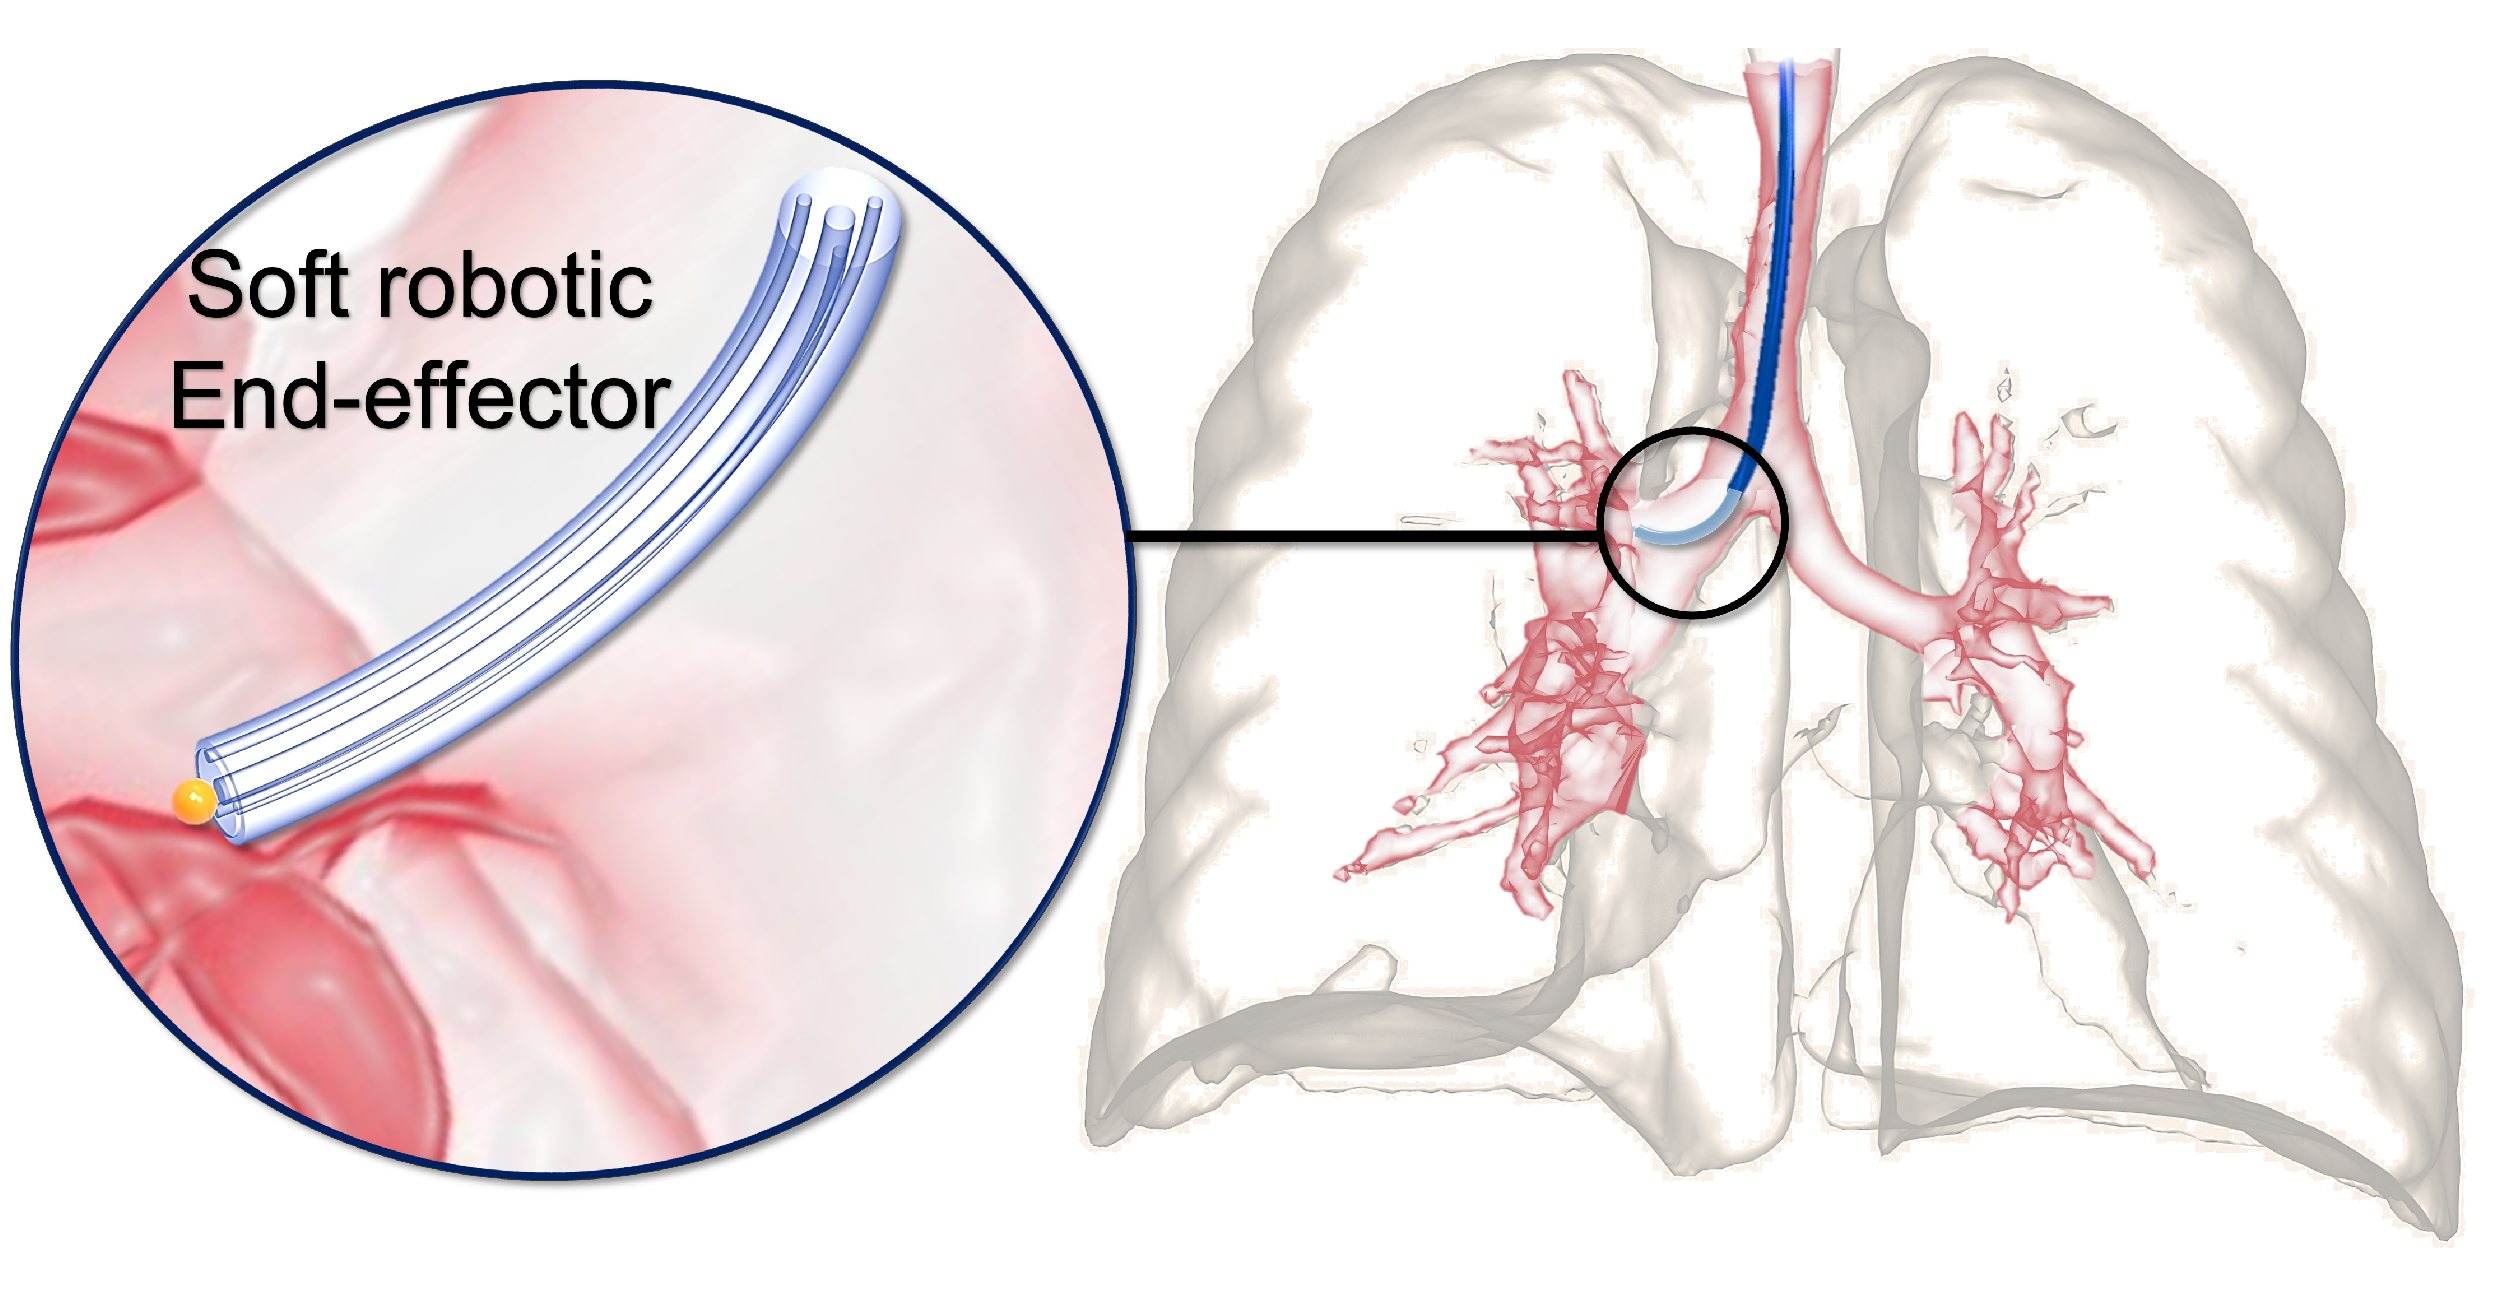

1.1. Background

1.2. Related Studies

3.1. Soft Robot Design